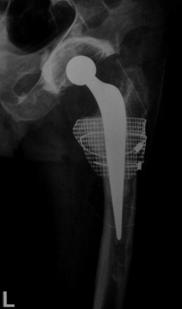

S-au folosit trei tipuri de proteza de revizie: Exeter (8 cazuri); Modular (9 cazuri); DLS (21 cazuri); acest lucru fiind evidentiat in Fig. nr. 2.2.3.

Fig. Nr. 2.2.3. - Repartitia tipurilor de proteza utilizate in cadrul interventiei de revizie.

Nu a existat o indicatie speciala pentru folosirea unui anume tip de proteza, alta decat existenta protezei in stocul de materiale al spitalului la momentul respectiv a unei proteze de lungime corespunzatoare depasirii defectului.